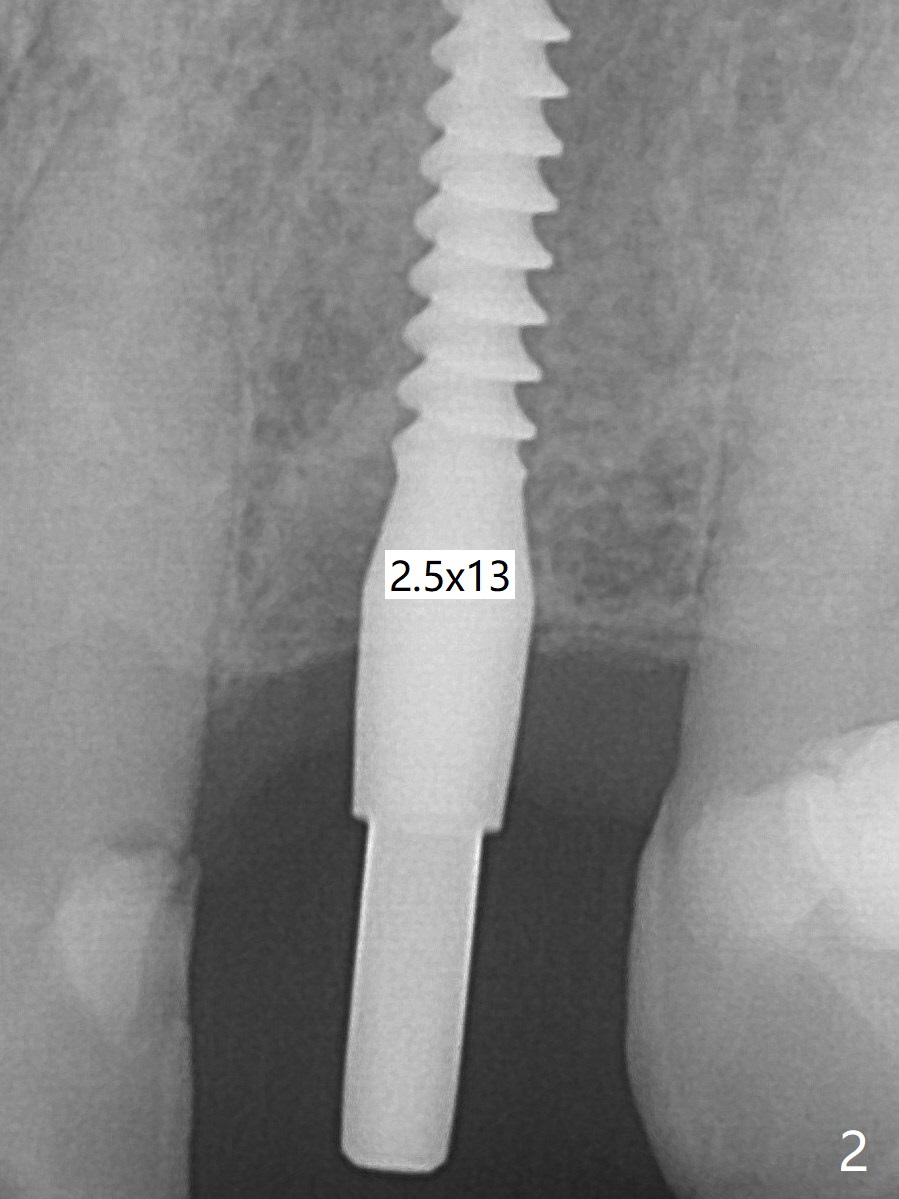

After undersized drilling in depth at #10 (2.2x13 mm (10.5 mm offset), Fig.1), a 2.5x13 mm 1-piece implant is placed with hand driver (Fig.2,3). The implant remains stable 5 months postop (Fig.6). The implant seems to be flexible before heavy occlusal reduction; note the periimplant micro-space (Fig.7). The patient is a bruxer.